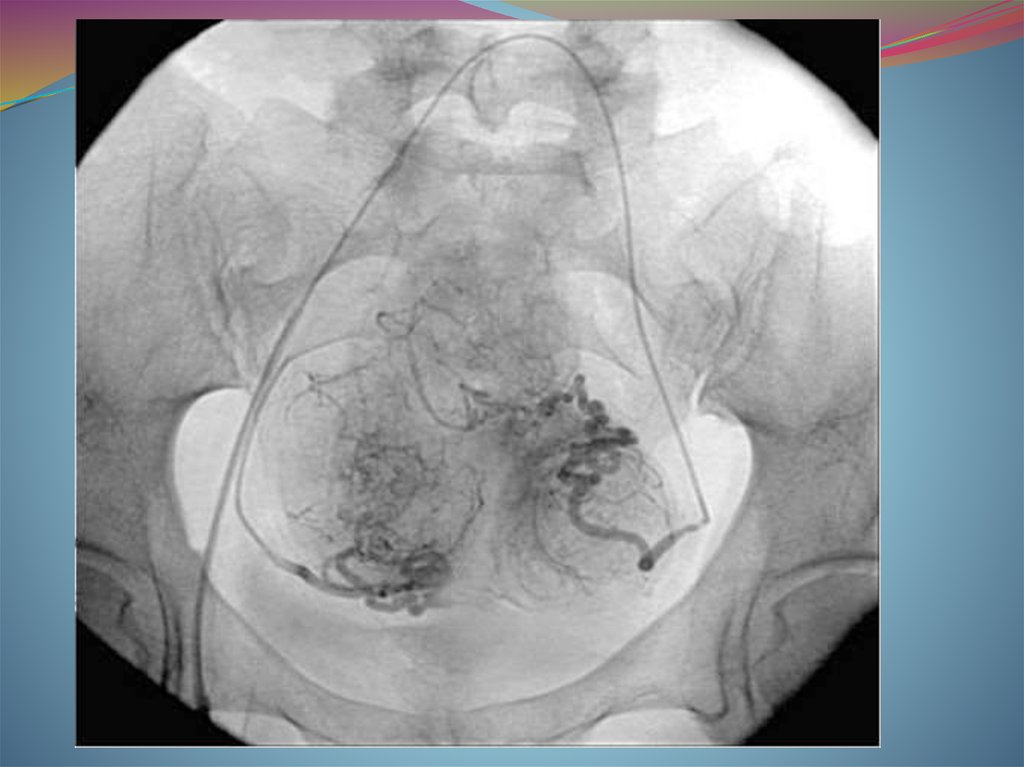

27. ЭМА

современный способ

лечения миомы матки

без хирургической

операции. Эффект

достигается за счет

перекрытия кровотока в

узлах миомы с помощью

специального препарата,

который вводится в

артерии матки по тонкой

трубке (катетеру) через

бедро.